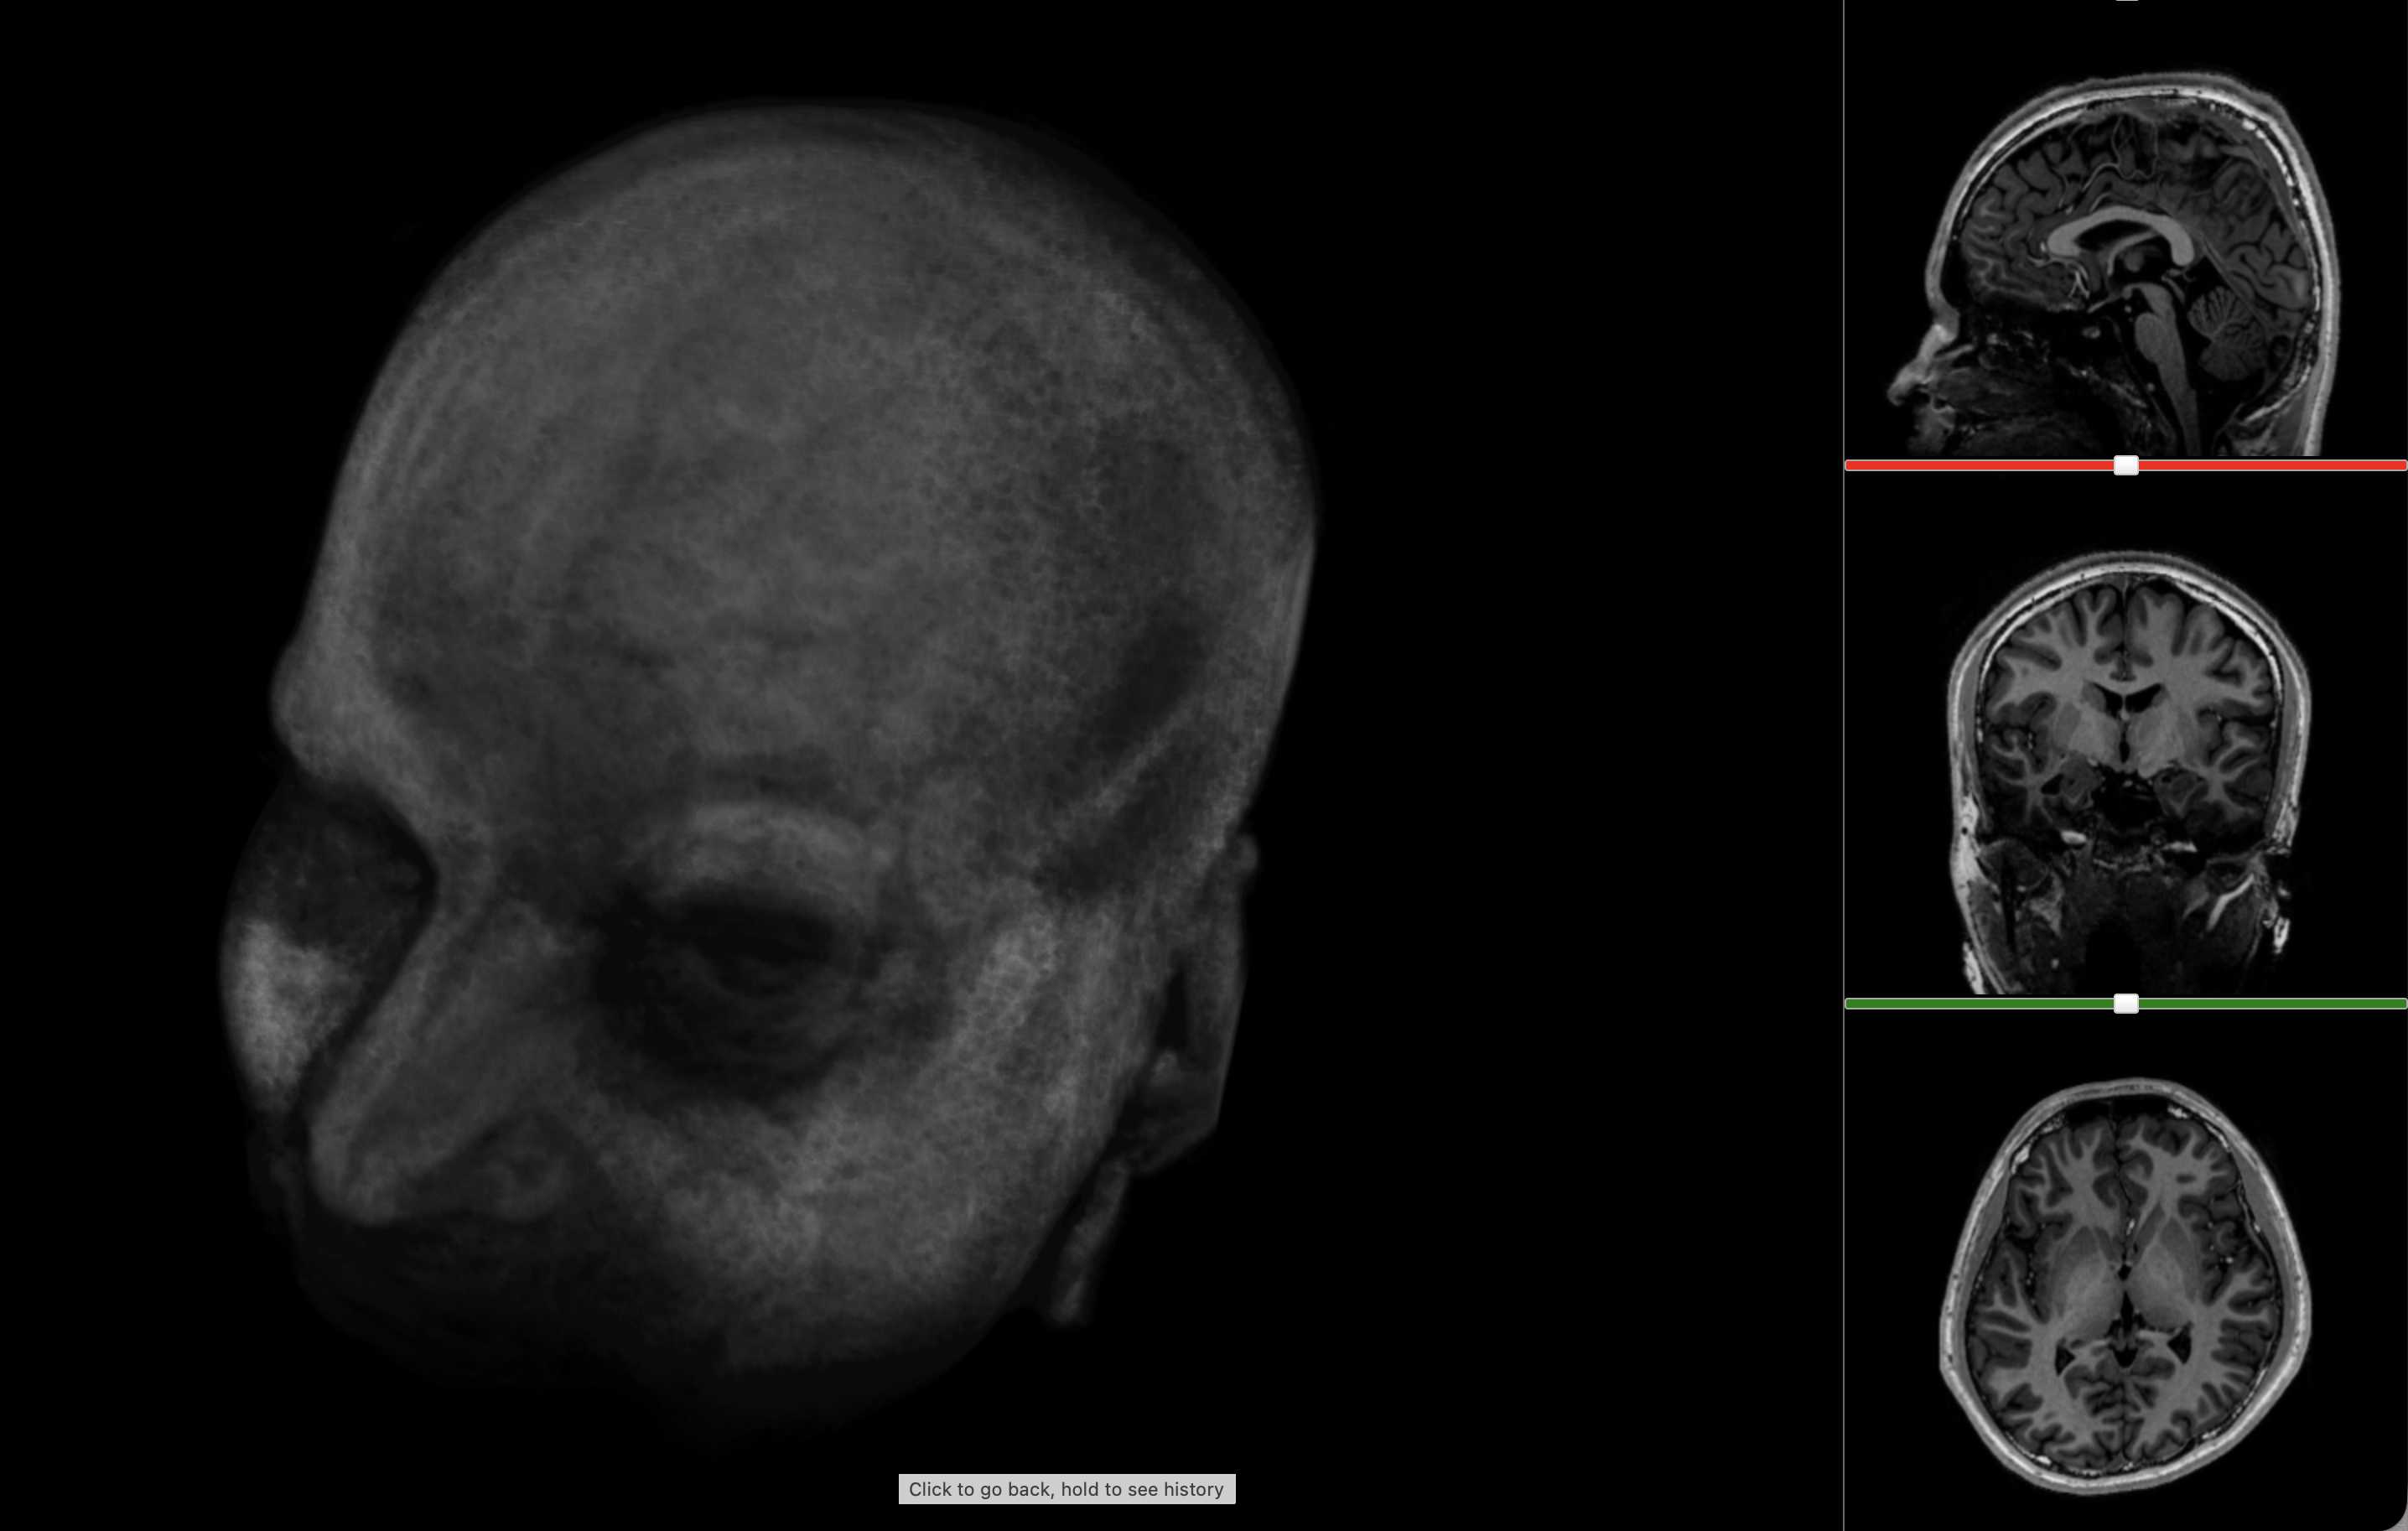

Turning anatomy into 3D models

Eventually I started thinking about turning this information into a 3D model. Unfortunately, FreeSurfer doesn’t provide 3D meshes out of the box. I had only:

- Cortical surface files: a map of the pial surface of the brain

- Surface annotations: annotations for the aforementioned cortical map, associating regions with names

- Volumetric segmentations: descriptions of which voxels in the 3D structure of my brain corresponded to which parts

To extract the models, I used the volumetric segmentations, essentially demarcations of where exactly each region was. The strategy was:

- Isolate one label as a binary mask

- Crop to its bounding box

- Run a marching cubes algorithm to create a 3D surface that would fit the label boundaries

This created quite clean 3D models that could be used with Three.js, 3D printing software or any model viewer. The remaining work was mostly pragmatic - I had to reduce the size of the model to ensure it would load quickly on the website. This involved decimation to reduce face count and smoothing to remove faceting (essentially 3D pixelation).